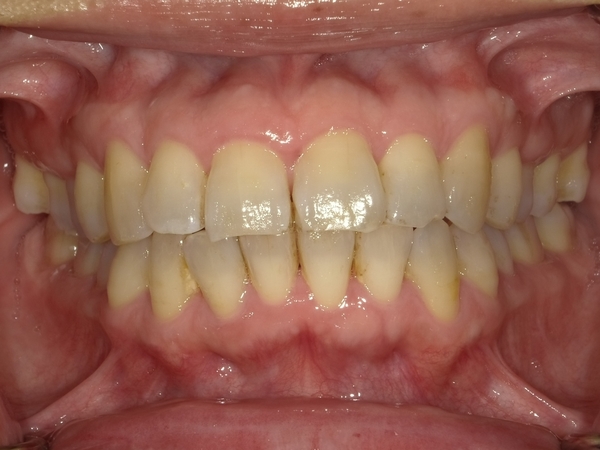

◯ご相談内容:歯がでたり引っ込んでいたりする◯矯正の種類:マウスピース型矯正「インビザラインGO」◯治療期間:17週間◯治療費用:44万円(税込)